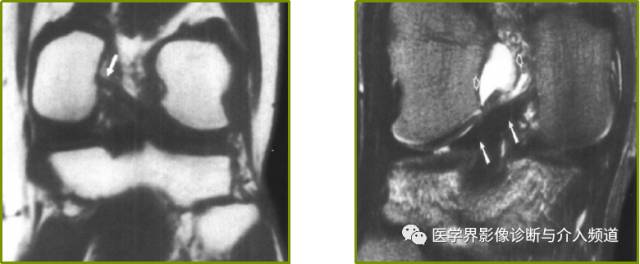

半月板小骨的病因尚不确定,但可能是创伤后或残留的结构,可能无症状或与局部疼痛有关。它们最常见于内侧半月板后角内;在平片上经常被误认为是游离体。在MRI能够显示半月板小骨位于半月板内,并容易误诊为半月板磨损并撕裂。

在T1加权矢状图像上,可见骨化(箭头)位于内侧半月板的后角内;